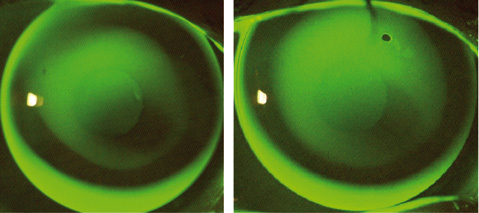

Vergleich KC 20 – KAKC-N

KC 20 (AS 9 7,45/9,2) KAKC-N (7,45/9,2)

Die Anwendung einer KC 20 empfiehlt sich nur noch bei Nachversorgungen. Bei Neuanpassungen eignet sich die KAKC deutlich besser, da sich bei Verschlechterung fast alle Stadien mit einer KAKC-Geometrie weiterversorgen lassen. Das Fluobild einer KC 20 AS9 und einer KAKC-N sind sehr ähnlich, wodurch eine Umstellung auf die KAKC erleichtert wird.